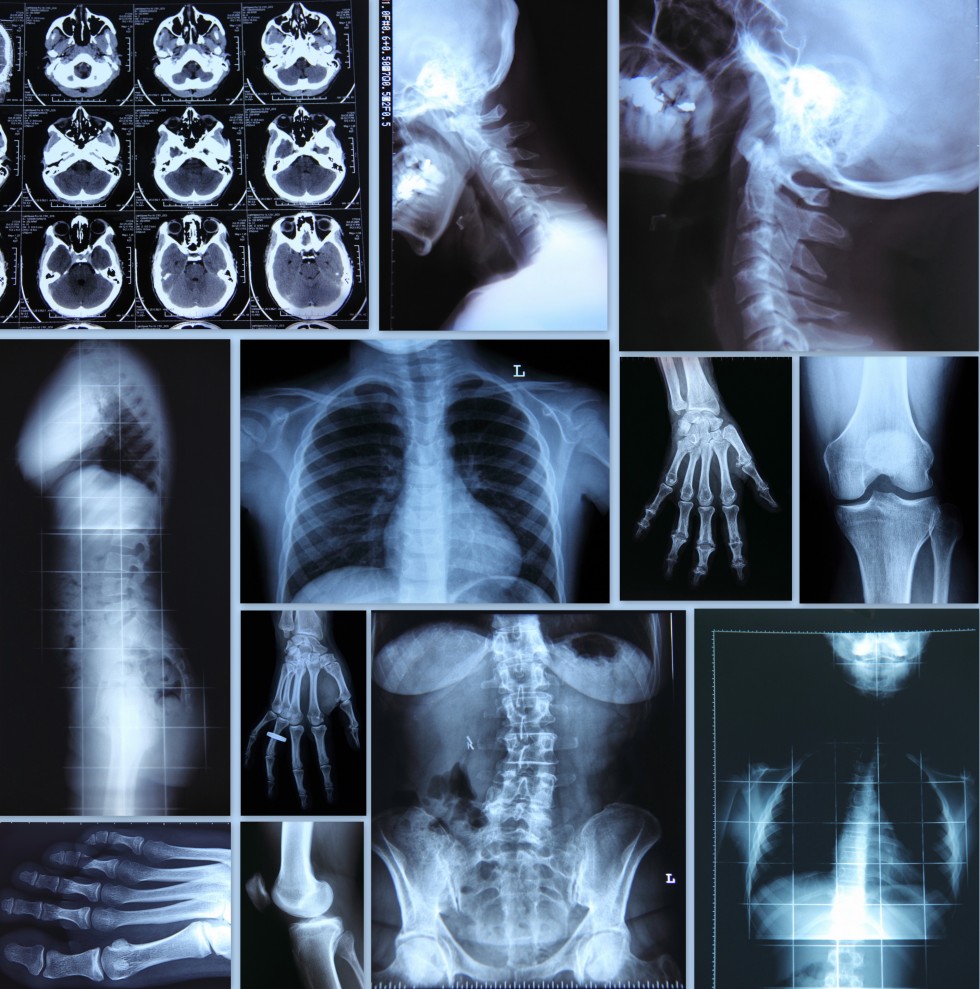

A radiologist is a medical doctor specializing in diagnosing and treating diseases through reading and interpretation of medical images such as X-rays, MRIs, Computed Tomography (CT) scans, mammograms, etc. Many years of training are required to be able to diagnose the presence of tumors and other abnormalities with a low rate of errors. Radiologists have at  least five to six years of specialized training (residency) after becoming a medical doctor.